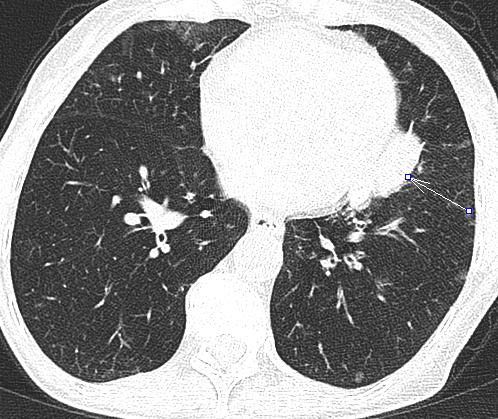

Symptoms: recurrent pulmonary infections treated with antibiotics, dyspnoe, weight loss

affects usually the upper lobes predominantly

predominantly peripheral consolidations with surrounding ground-glass opacity; the septal thickening is more common in acute eosinophilic pneumonia